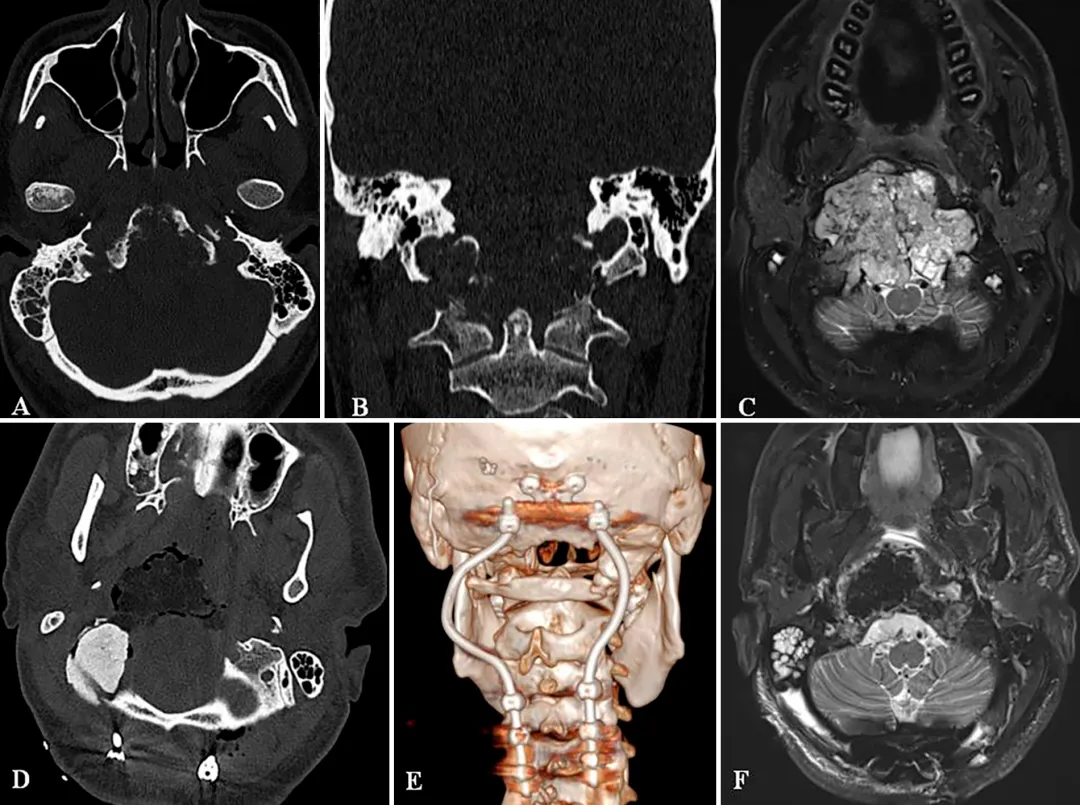

患者26岁,男,主诉颈部疼痛、严重吞咽障碍、双侧舌下神经麻痹(右侧完全麻痹伴舌萎缩,左侧部分麻痹)。MRI和CT扫描(图3A-C)显示较大颅颈交界区脊索瘤,肿瘤较大直径达10cm、瘤体积96.5cm³,肿瘤并向双后外侧延伸浸润性生长,较多侵犯右侧,肿瘤延伸至椎前间隙、下斜坡、双侧枕骨髁、一颈椎C1的前弓以及C2的齿状突,较大肿瘤压迫脑干和双侧椎动脉移位,并向硬膜内压迫扩张。

使用Roy-Camille技术进行枕颈融合术(C0-C3-C4-C5),固定根钉以曲线方式横向弯曲,为后续质子治疗创造一个无金属的定位及治疗通道。术后CT和MRI显示肿瘤完全切除。病理证实为典型脊索瘤。在术后恢复中,患者吞咽功能好转和颈部疼痛缓解。8周后,他接受了质子治疗。

A和B:术前CT扫描显示颅颈交接区脊索瘤,侵犯斜坡-枕髁并呈溶骨性损害。C:术前MR显示肿瘤较大延伸,并浸润长入硬膜内的脑实质。D:术后CT显示PMMA枕髁重建稳定良好。E:术后三维CT显示C0-C3-C4-C5枕颈融合稳定,与根钉弯曲有利于PBRT治疗。F:术后MR显示全切肿瘤和脑干延髓占位压迫得到解除。